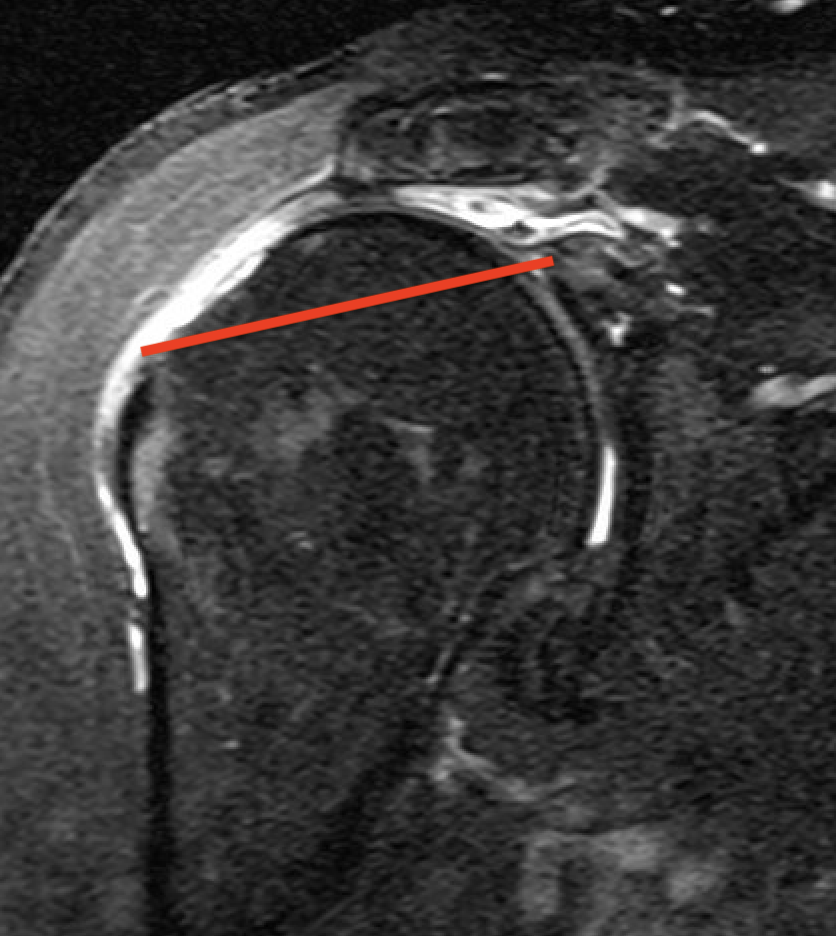

Tangent sign

- sagittal MRI

- line connecting superior coracoid and superior border scapular spine

- if supraspinatus muscle is below line, there is significant atrophy

- positive tangent sign / significant atrophy associated with larger tears / irrepairable tears

Negative tangent / no atrophy Positive tangent / significant supraspinatus atrophy